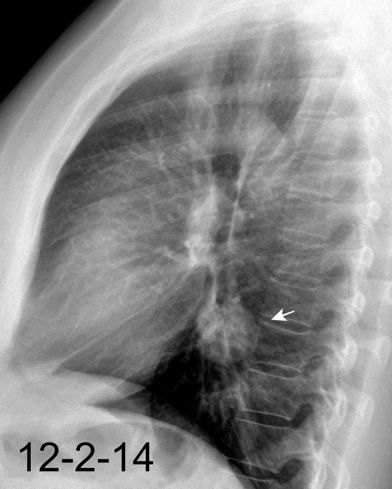

30 años

Borramiento de la banda PARA-aórtica por AdenoCa. de LII, no visible en 2005

Colapso de LII. TC: secreciones bronquiales.

Endoscopia tapón mucopurulento extraído